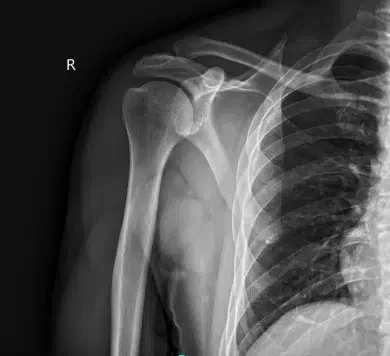

He presented results for the right shoulder’s x-ray that showed acromioclavicular joint arthropathy. For his left hip, x-ray have shown mild acetabular over coverage. For cervical spine, mild reduction in disc space.

X-ray right shoulder minimum 2 views